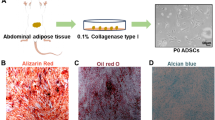

Trilineage differentiation potential of hUC-MSCs

The multidirectional differentiation capabilities of hUC-MSCs were detected using commercial MSCgo™ differentiation kits (BI, Israel). hUC-MSCs were seeded in a 48-well plate at a density of 1 × 104 cells/well and cultured in adipogenic, osteogenic, or chondrogenic differentiation induction medium. The induction medium was changed every 3 days. On day 21, the cells were fixed and stained with Oil Red O for adipocytes, Alizarin red S for osteocytes, and Alcian blue for chondrocytes (Servicebio, China).

hUC-MSCs’ identification and its characteristics

Frozen hUC-MSCs were resuscitated and expanded under standard conditions. After 6 h of resuscitation, the cells showed adherence and rapid proliferation. After 48 h of culture, the cells reached 80% confluence with fibroblast-like morphology and spindle-shaped appearance. There was no discernible variation in morphology or plastic adhesion characteristics until passage 5 (Fig. 1A).

Identification of hUC-MSCs. A Growth and morphology of hUC-MSCs at first passages (P1) and fifth passages (P5) respectively (scale bar = 500 μm). B Cell proliferation of P1 and P5 was assessed by the CCK-8 assay (n = 3). C The markers for hUC-MSCs were detected by flow cytometry and hUC-MSCs were positive for CD73, CD90, and CD105, while negative for CD11b, CD34, and CD45 (n = 3, all histograms show specific membrane antigen in green and control isotype-specific IgGs in red). D hUC-MSCs differentiation potentials. Adipogenic differentiation capacity (Oil Red O staining), osteogenic differentiation capacity (Alizarin Red staining), and chondrogenic differentiation capacity (Alcian blue staining) (scale bar = 250 μm) (n = 3)

CCK-8 was used to detect the variation in the proliferation of hUC-MSCs from passages 1 and 5. The results showed no significant difference in the growth of hUC-MSCs after 5 passages (Fig. 1B).

Flow cytometry was used to identify hUC-MSC phenotypes. hUC-MSCs were positive for the canonical MSC markers CD73 (99.37%), CD90 (99.16%), and CD105 (99.19%), and negative for the hematopoietic markers CD11b (0.49%), CD34 (0.36%), and CD45 (0.34%) (Fig. 1C), indicating that hUC-MSCs express most of the consensus MSC markers, suggesting that these cells possess MSC-like characteristics. The differentiation potential of hUC-MSCs was also examined. As shown in Fig. 1D, Oil Red O, Alizarin red S, and Alcian blue staining revealed the adipogenic, osteogenic, and chondrogenic differentiation abilities of hUC-MSCs, respectively.